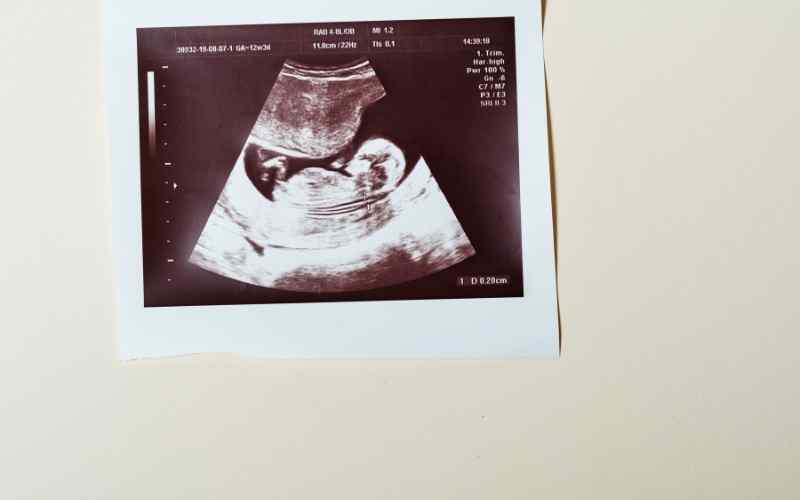

Bà bầu tháng thứ 5 cần chú ý về lịch khám thai định kỳ của mình do bác sĩ hẹn. Thời điểm khám thai nằm trong tuần 17-20 của thai kỳ. Trong lần khám thai tháng thứ 5, bác sĩ sẽ kiểm tra bụng, cân nặng, huyết áp, vú, da, tình trạng phù nề tay, chân, tĩnh mạch và đặc biệt là kích thước, chiều cao tử cung cùng tình trạng phát triển của thai nhi.